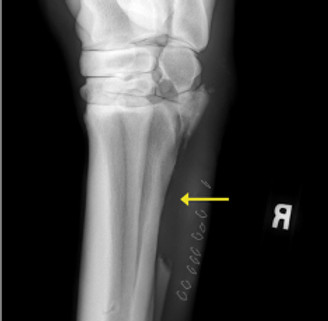

A 9-year-old Thoroughbred Cross mare was presented to one of our Steinbeck Peninsula Equine Clinics veterinarians for a wound just below her hock. Upon evaluation in the field, the horse was grade 4/5 lame in the right hind (lame at the walk). Close examination of the wound along with radiographs (x-rays) showed a comminuted fracture (broken into many small pieces) of the lateral (outside) splint bone with high suspicion of joint involvement.

Yellow arrows point to multiple fracture lines on the radiograph from initial evaluation.

The yellow arrow on this post-operative radiograph points to where nearly half of the affected splint bone was removed.